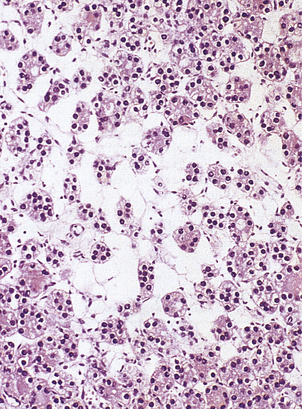

In addition to those ‘functioning’ adrenal cortical adenomas that present by causing Cushing’s or Conn’s syndromes, a clinically unsuspected ‘non-functioning’ adenoma occurs in about 2% of adults. The adenoma is a pale yellow circumscribed nodule, perhaps 20–30 mm in diameter (Fig. 17.16). The cells have clear cytoplasm owing to their high lipid content (Fig. 17.17).

image

Fig. 17.16 Adrenal cortical adenoma. A pale-coloured fleshy nodule in the adrenal cortex is displacing the medulla and stretching out the rest of the cortex.

Fig. 17.17 Cells in an adrenal cortical adenoma. The cells are large with clear cytoplasm and compact nuclei.